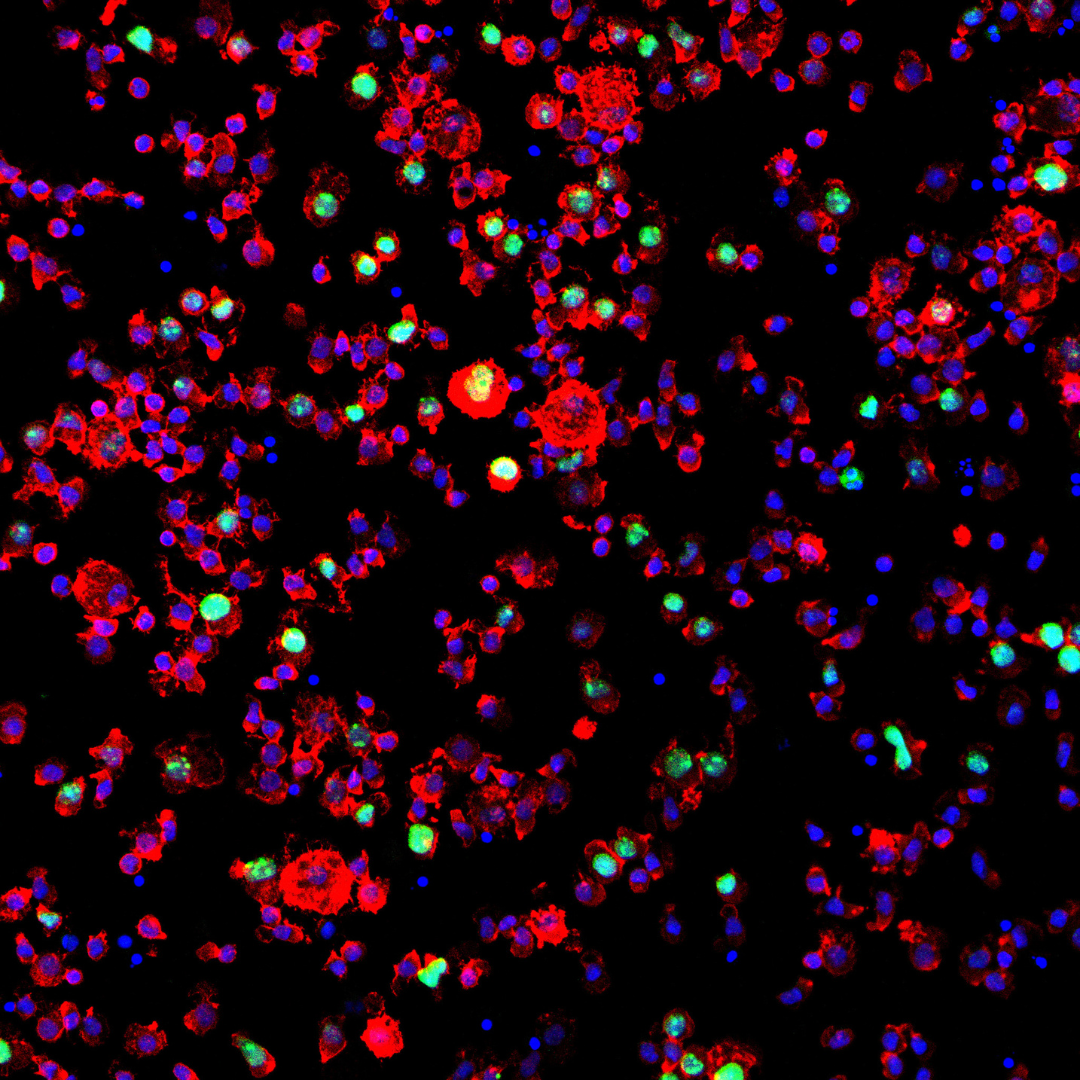

Buy My Cancer

Za nietypowe myślenie i nieszablonowe podejście wykorzystujące sztukę i ilustrację w nowoczesnym świecie technologii. Szczególnie warto to docenić, bo dla obu bardzo ważne są nowe drogi dotarcia do odbiorcy i fajnie, że twórcy kampanii o tym myślą. Wyróżnienie należy się za nowoczesne podejście, za “spojrzenie inaczej”, za przecieranie nowych dróg wykorzystania ilustracji i znalezienie nowego miejsca we współczesnym, zdigitalizowanym świecie. I na koniec, oczywiście, za szczytny cel, bo jeśli ilustracja może pomóc, to cieszy mnie to jeszcze bardziej.